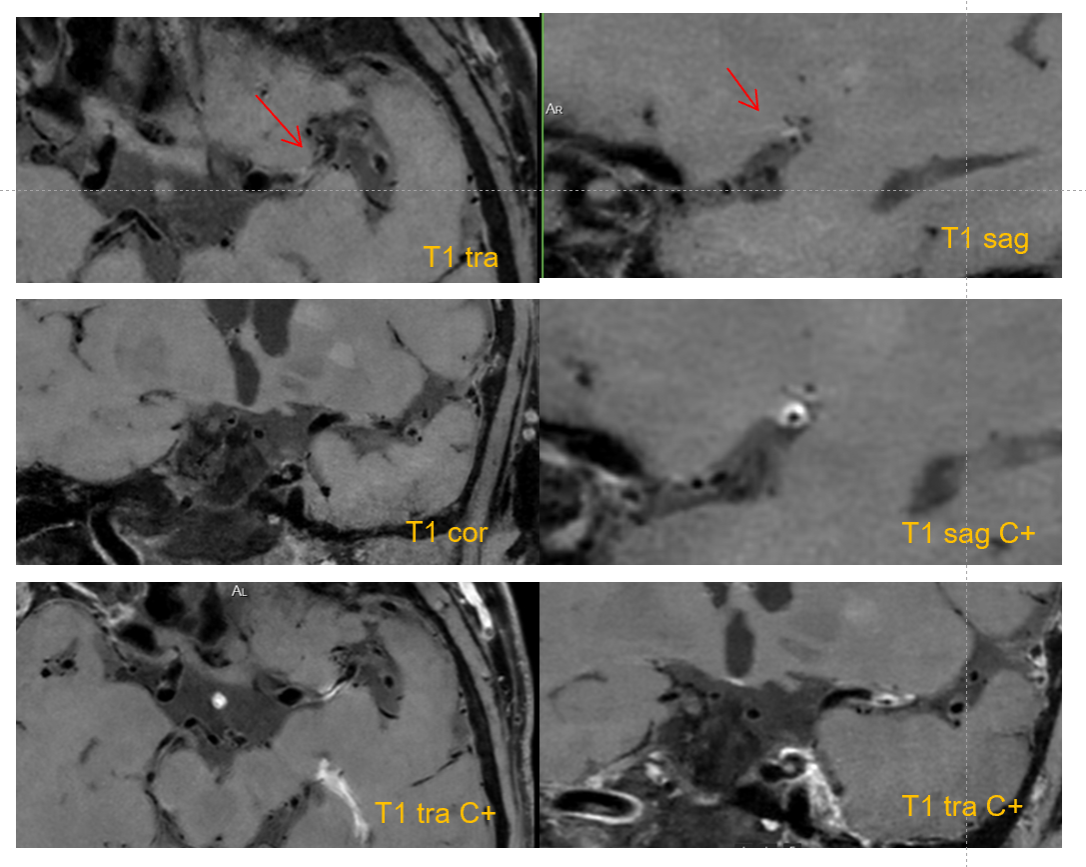

左侧大脑中动脉M1段节段性管壁向心性增厚伴出血可能,增强明显强化,考虑为责任斑块,伴管腔重度狭窄

M1段分叉处动脉瘤,清晰显示瘤体与血管之间的关系;增强后瘤壁强化,提示动脉瘤破裂风险